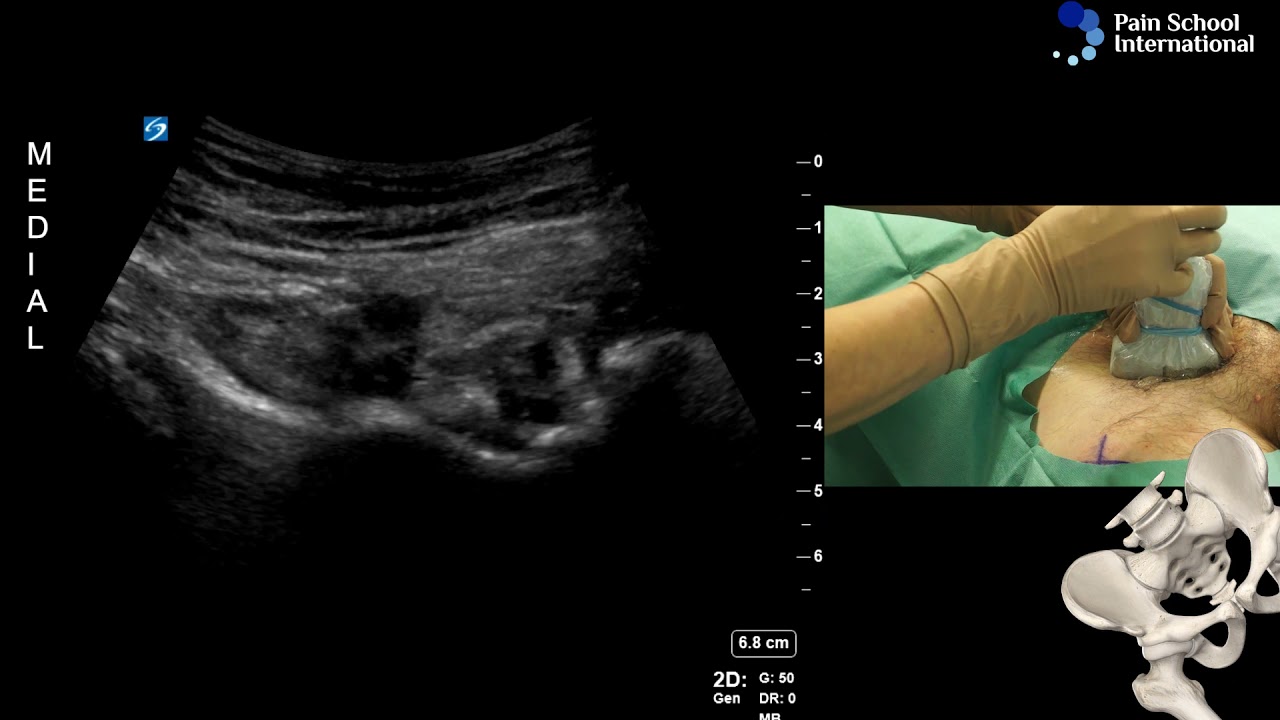

Chronic Hip Pain - Dr. Amr Badawy, Orlando Pain & Spine Center

Описание: Dr. Amr Badawy explains Radio Frequency Ablation treatment for chronic hip pain is performed at Orlando Pain & Spine Center.

Minimally Invasive Hip Pain Relief: Femoral and Obturator Nerve Radiofrequency Ablation Explained

Cooled Radio Frequency Ablation (RFA) of the Hip Joint #SIDTALKS

Dr Agnes Stogicza - Cryoablation E-Learning Seminar 1 Session 1: Hip denervation